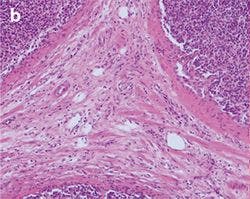

Figure 5: Stained Tissue Section b

Differences between halogen lamp (a) and LED illumination (b) lead to tissue stainings shifting to blue, both through the oculars and on the screen. Adding a CC filter (c) mitigates the issue, but still gives a yellowish appearance.